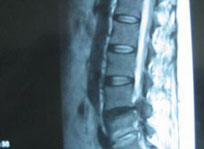

脊柱MRI

MRI可准确评价脊柱和各种病理情况,T1加权成像适用于评价髓内病变、脊髓囊肿、骨破坏病变,而T2加权成像则用于评价骨唇增生、椎间盘退行病变与急性脊髓损伤。